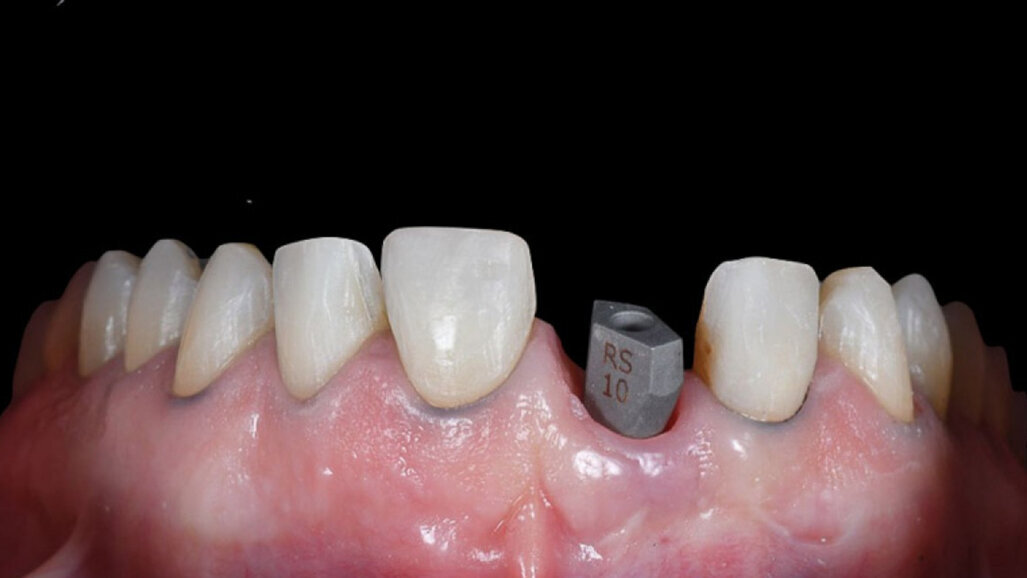

De 39-jarige patiënt kwam bij ons met het verzoek om zijn glimlach te verbeteren. De eerste esthetische analyse bracht het volgende aan het licht:

• disproportionele spacing;

• aanwezigheid van diasteem;

• verkeerde inclinatie van de tandassen;

• te veel ruimte tussen de buccale vlakken van de elementen in de bovenkaak en de mondhoeken (afb. 1, 2).

Afb. 2